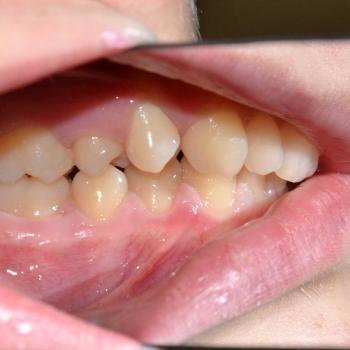

Benjamin és édesanyja az alsó és felső fogíven tapasztalható torlódás miatt kerestek fel, ám az első vizsgálat alkalmával fény derült a jobb felső 5-ös fog csírahiányára, mélyharapásra és féloldali Angle II-es harapási eltérésre is.

A kezelést hagyományos fém fogszabályozóval kezdtük el, melyet bite turbo harapásemelővel egészítettünk ki. A kezelés későbbi fázisában a szimmetria megteremtése érdekében eltávolításra kerül a bal felső maradó 4-es fog is és ezzel párhuzamosan különböző intermaxilláris gumihúzásokat vezettünk be.